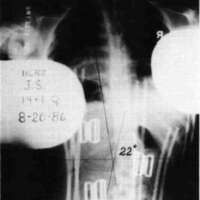

Let us now look at two examples were these stabilizing schemes have been simultaneously applied. Fig. 10a is a photo of a 12 year old boy with muscular dystrophy, sitting as he was presented to us. Fig. 10b shows the sitting support system properly applied. The corset is entirely independent; it is not attached to the seat. Fig. 10c and Fig. 10d compare his A-P spine x-rays without and with the orthotic system. The lateral tilt of his pelvis is reduced from 30 degrees to 14 degrees. The Cobb angle of his scoliosis was reduced from 65 degrees to 35 degrees. Curve control of this magnitude is not unusual as long as the deformity is still flexible. Fig. 11a is the x-ray of J.S., a 14 year old girl with cerebral palsy. She presented a right thoraco-lumbar scoliosis of 38 degrees and a rightward pelvic tilt of 8 degrees. Her shoulders were tilted 13 degrees to the left partly because she used her right arm for propping to avoid falling to the right. We provided her with a soft corset and the Gillette Sitting Support Orthosis. The Sitting Support Orthosis was to provide pelvic control and bilateral "propping" support. It had no head rest or anterior support. The x-ray taken just after fitting shows pelvic tilt reduced to 2 degrees (Fig. 11b), the Cobb angle of the scoliosis reduced to 22 degrees, and shoulders leveled. Both hands were free to function, and she said she could breathe deeper.

Figure 11a. X-ray of J.S., a 14 year old girl with cerebral palsy.

Figure 11b. J.S. provided with a soft corset and the Gillette Sitting Support Orthosis.